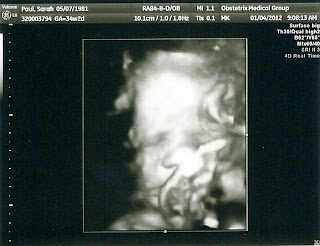

We went for an ultrasound at the high risk doctor today and everything looked great. She is head down! They said she is measuring 5 pounds, 10 ounces. According to the baby tracker websites, this is about a pound more than average for 34 weeks. Yikes. Claire was very active until right when the tech turned the machine to 3D. She then decided to take a nap with her hand covering half her face. Ryan and I were disappointed we couldn't see her whole face but we still think she looks a lot like Cason if these pictures mean anything.